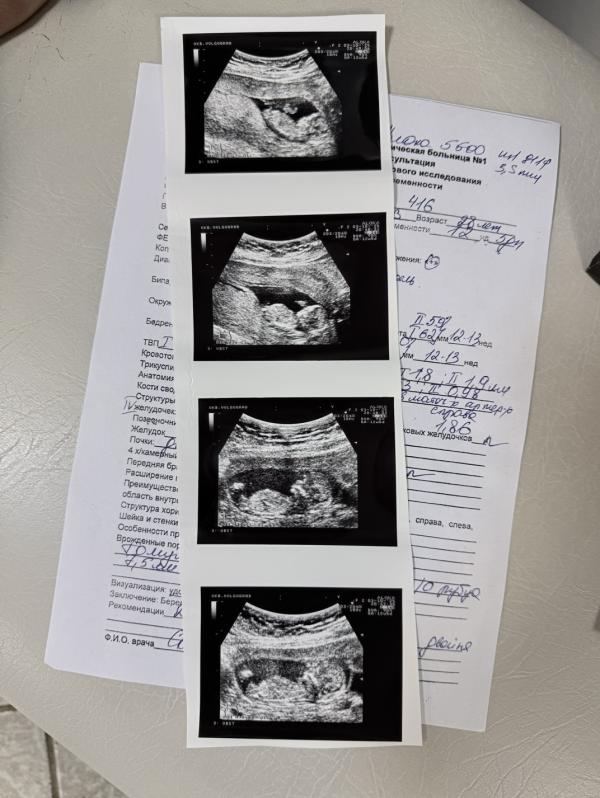

post image 1

post image 2

Первый скрининг пройден ✅

Наши малыши растут и все хорошо❤️

Мальчик по нижнему фото ☺️

Один точно мальчишка

По фото похоже на мальчишек